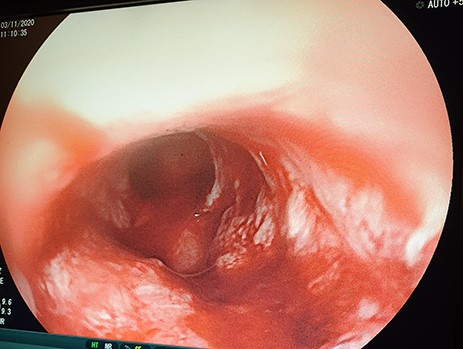

The patient was scheduled for GFT insertion. Under aseptic technique, with the patient in supine position, 24 Fr urinary catheter as an improvised GFT was inserted in Stamm manner, haemostasis achieved, abdomen closed in layers and dressed (Fig. 9). There was no ascites and mesenteric lymph nodes were not palpable. After the procedure the patient was discharged home on the second day with analgesics and was booked for a surgical outpatient clinic appointment after 2 weeks.

24Fr urinary catheter as an improvised gastrostomy feeding tube.